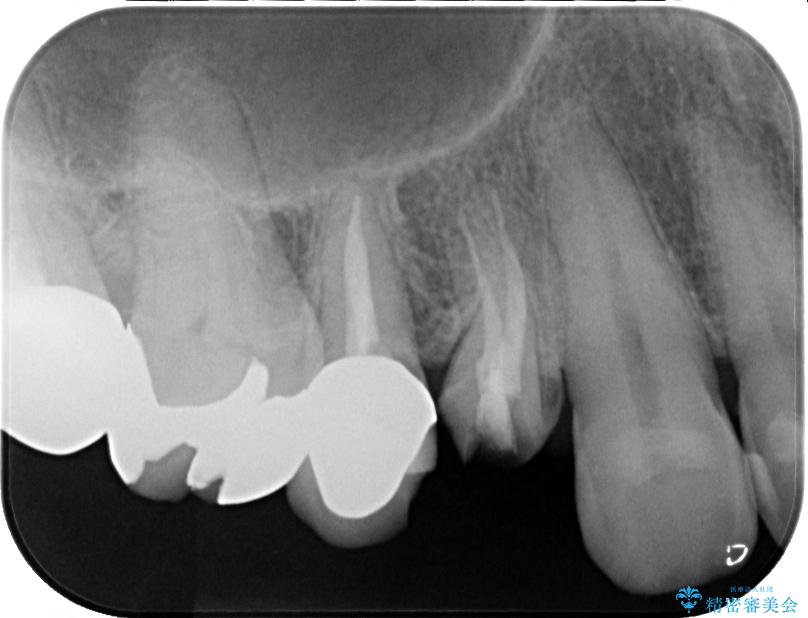

診察の結果、被せもの(クラウン)だけでなく、土台(コア)ごと外れてしまっている状態でした。根管治療済みの歯ではありますが、今回患者様のご希望により、根管治療の再治療は行わず、補綴処置のみを行う方針となりました。

治療前

• 自然な美しさと強度を両立!右上小臼歯の被せもの脱離に対する審美補綴治療 治療前画像